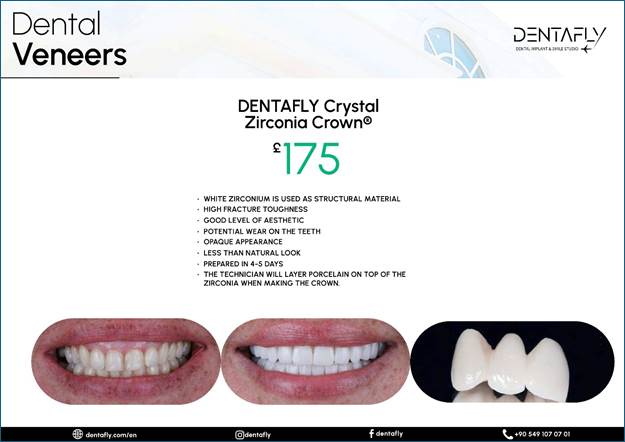

To AI Edge Ok I went to turkey to Antalya

to a company called Dentafly but before I left I sent picture through what’s

app of my teeth and received a quote of 1325 pounds the invoice stated I will

receive STRAUMMAN NEODENT IMPLANTS N ABUTMENTS

2 IMPLANTs but when I got there I see their head dentist and he

advise me to get better ones named Hiossen NH Hydrophilic Implants and one

extra crown which we never realized I needed. He quoted 375 for the extras.

The price of the crows is £125 pounds as in the invoice above, so he charged

an extra £250 pounds for the implant upgrades as I was told. I have got home now and

checked the first invoiced and it has a section with pictures and texted

titled as Dental Implants Which brands we are working with and

states Hiossen NH Hydrophilic Implants 490 pounds and Straumann BLX Implants

750 pounds. so, he charged me more and

give me rubbish ones by the pricing in their invoice. The image below is from the

invoice and proves the original Implant make!

The image provided below is

also from the first invoice and serves as evidence of the pricing listed in

their advertisements. It is important to note that there are six distinct

brands featured, accompanied by only three images. This potentially leads to

confusion, as each brand has its own unique pricing structure. Upon reviewing

their website, it becomes clear that these brands should each have their own

corresponding images; however, this is not the case. Furthermore, the layout is

compounded by the presence of only two divider lines, which implies that each

section contains multiple advertisements rather than a single advertisement

per brand. This setup undermines the clarity of the pricing information, as

it suggests a mix of prices for two different products within the same

section.

Evidence that these brands

should each have their own corresponding images, as they are their own brands,

is as below! https://dentafly.com/treatments/antalya-implant-treatment/